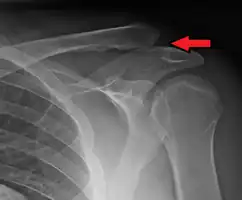

Type 3 -

Type 3 AC joint separation on plain X ray